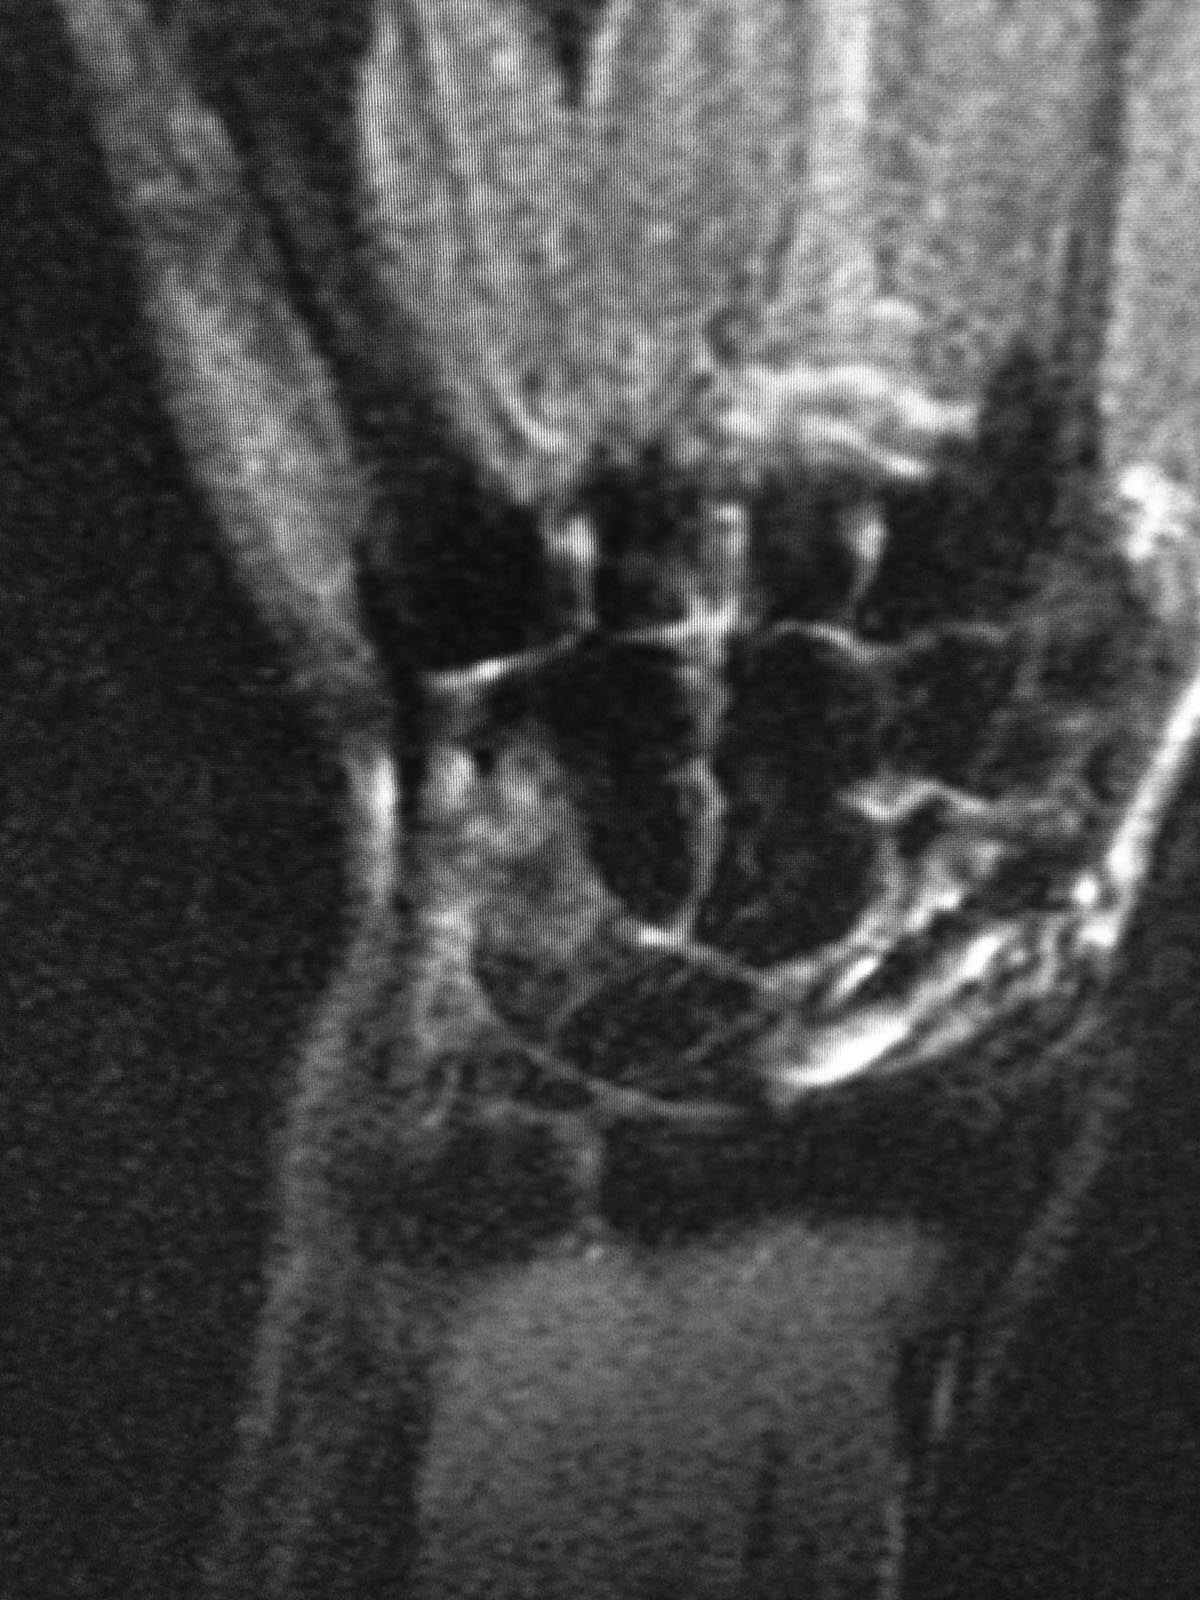

Здравствуйте. Мужчина 30 лет. Травма около 5ти лет назад, МОС винтом, в

данное время в проекции ладьевидной кости болей нет, осевая нагрузка на

1ю пястную кость безболезненная, боли беспокоят при пальпации в проекции

трехгранной кости и движениях в лучезапястном суставе (при пассивных и

активных движениях возникают острые боли, так же в проекции

трехгранной кости). На МРТ отмечаются проблемы в этой зоне. Со слов